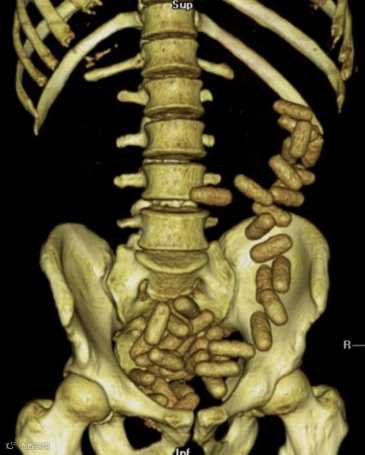

作为普通的放射科医生或技师,我们也可以在反诈、禁毒中尽自己的绵薄之力,尤其是看到这样图像时,请立即报警❗️❗️❗️

腹部CT扫描显示结肠(主要是降结肠、乙状结肠和直肠)有大量椭圆形高密度异物,这可不是“可爱的蚕宝宝”,而是小包分包的可卡因,大约有300-500g。